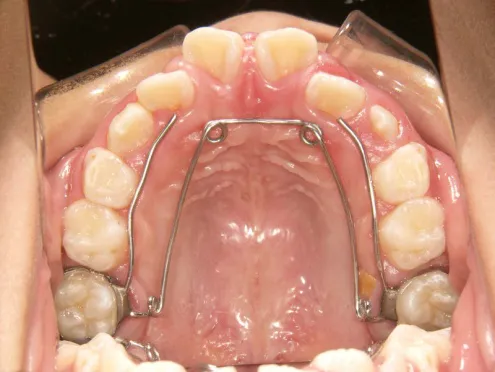

QH

BH

治療中➁拡大・前歯の並替え装置(写真はイメージ)